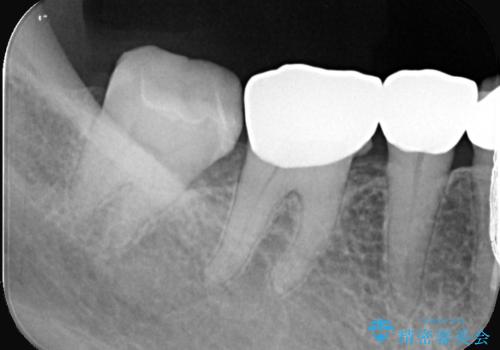

- 主訴:下の歯に詰まっている銀が笑うと見えて嫌だから白くしたい

右下7番目の歯に保険適用のメタルインレーが入っており、大きなう蝕などは認めなかったため概形は大きく変えずセラミックインレーへやり替えとなりました。

やり替える過程で古い裏層材やカリエスは全て除去し、新たにCR裏層を行っています。

セラミックインレーセット時はラバーダム防湿を行っています。